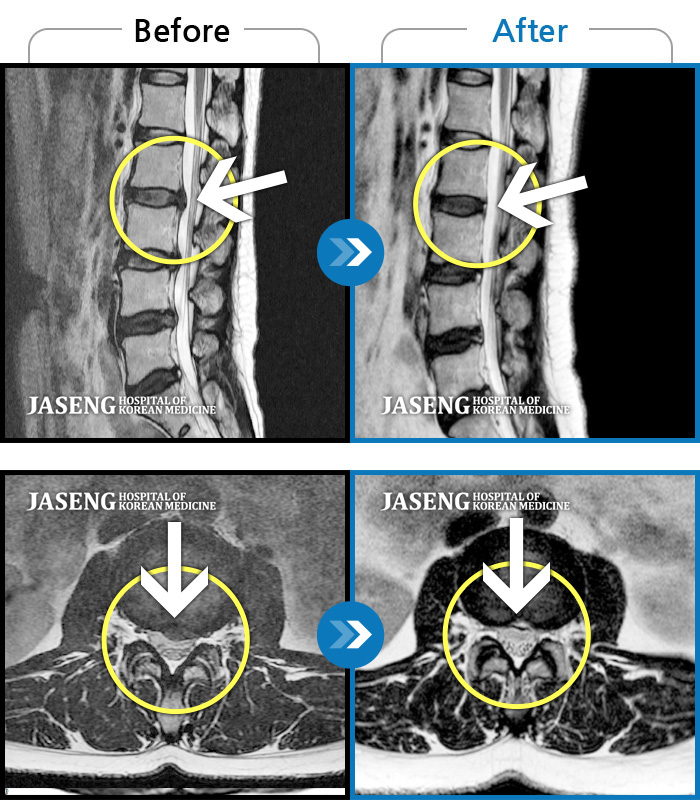

허리디스크

도움받은 사례

강남 · 강만호 원장

허리통증이 심해서 숙이기 어렵고 차에서 내리기 힘들었습니다.

촬영시기

2021.01.06 ~ 2025.03.10

2025.03.20

조회수 13,021